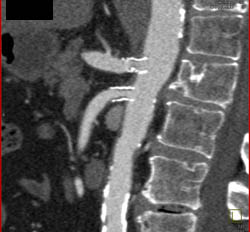

Metastatic Renal Cell Carcinoma to Liver and Pancreas- Arterial and Venous Phase Images